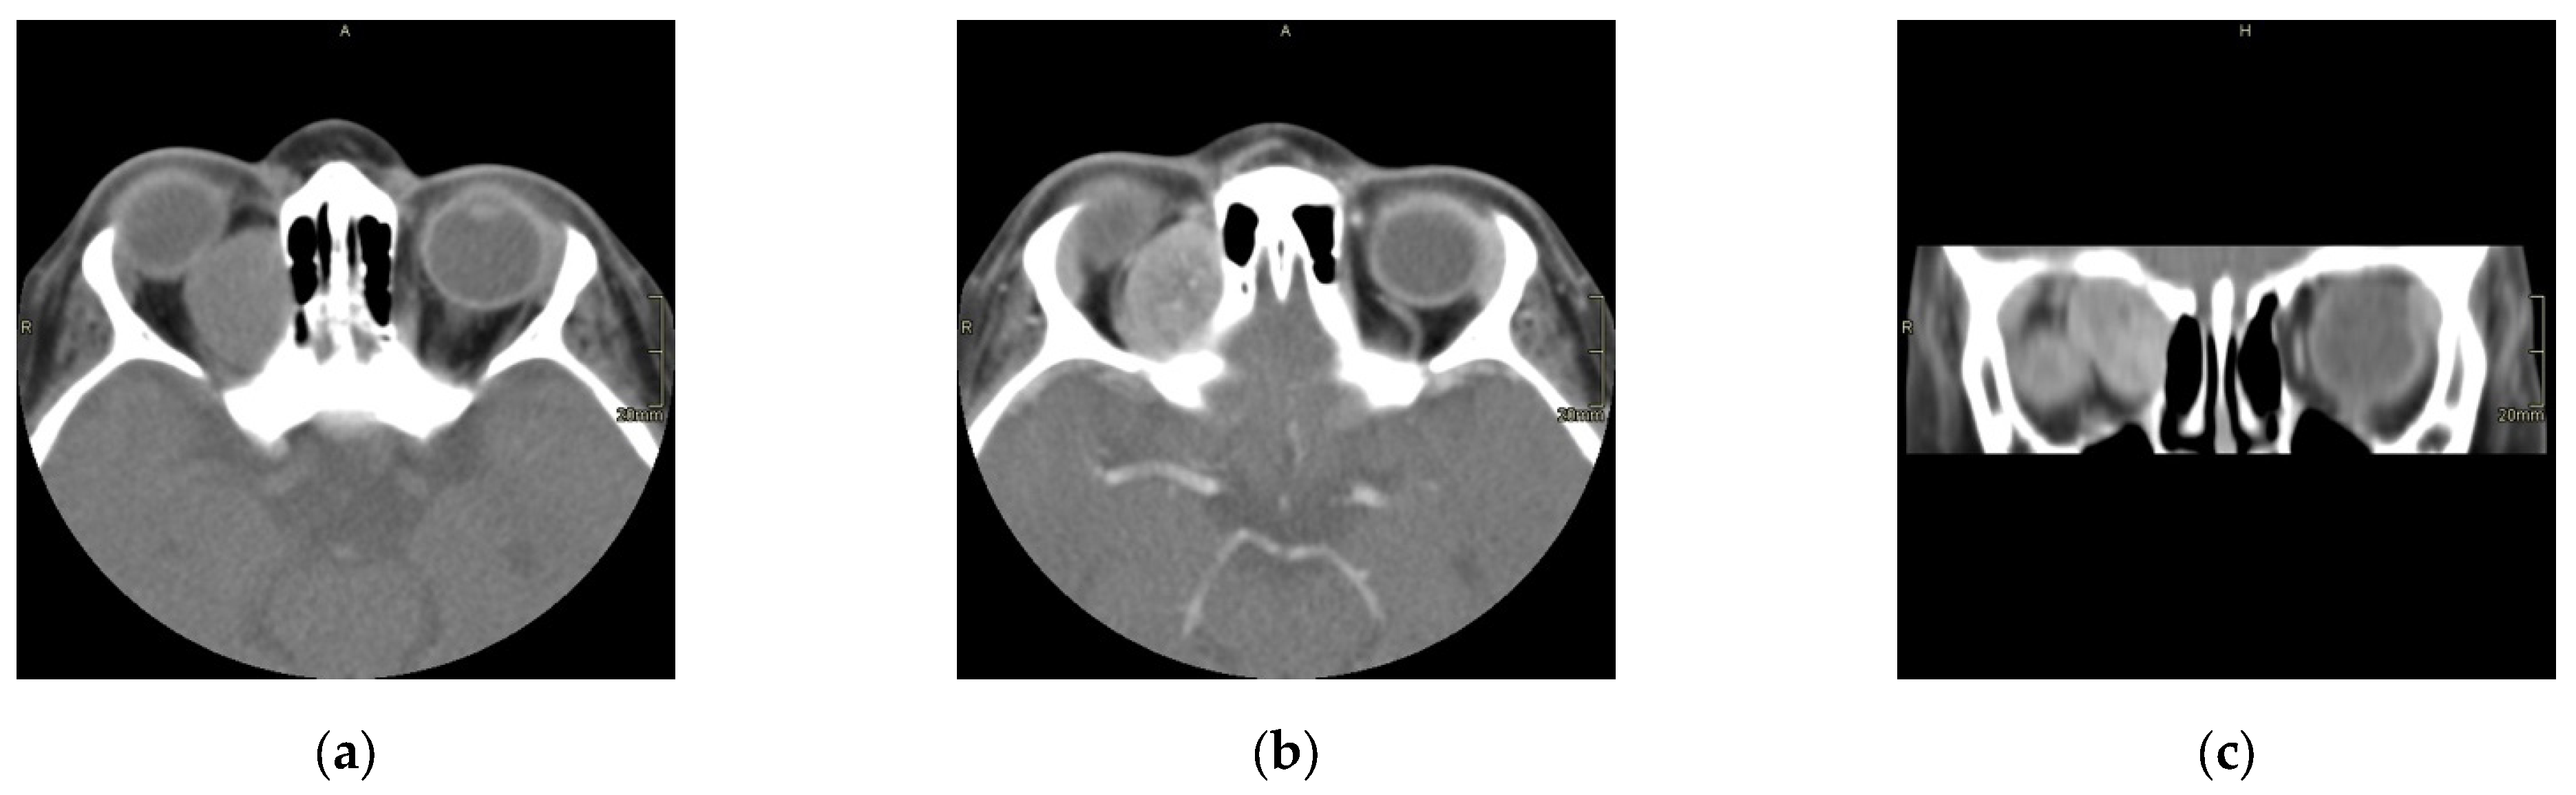

Overall survival (OS) and EFS were calculated in 39 patients. The 10-year OS rate in our series was 95%. The survival rate between 9 months to 10 years was 96% and that of cases at older ages (≥10 years) was 93%. EFS (10 years) was found to be 63% [Figure 4].

Figure 4. Event free survival curve; EFS is 63%. According to the curve at zero point, the chance of not experiencing the event is 92.3% because two cases had already shown treatment failure immediately after the primary treatment. At 12 months after starting the study, the chance of not experiencing the event is 78.6%.